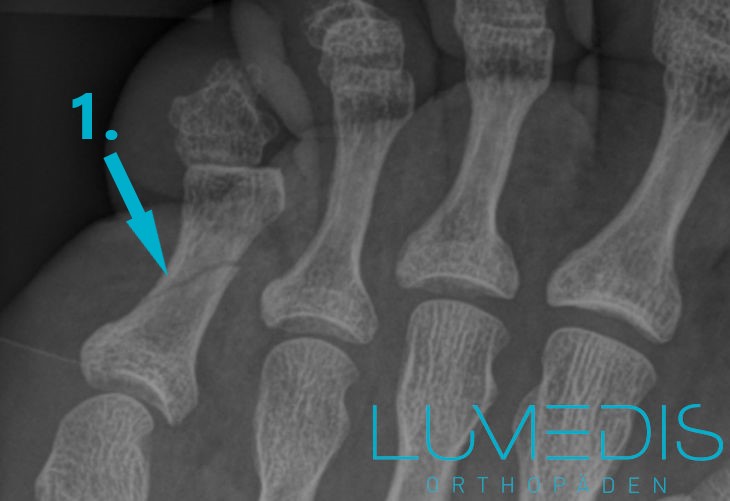

Röntgenbild Vorfuß:

Fraktur (Bruch) des dritten Zehs im Grundglied (türkiser Pfeil)